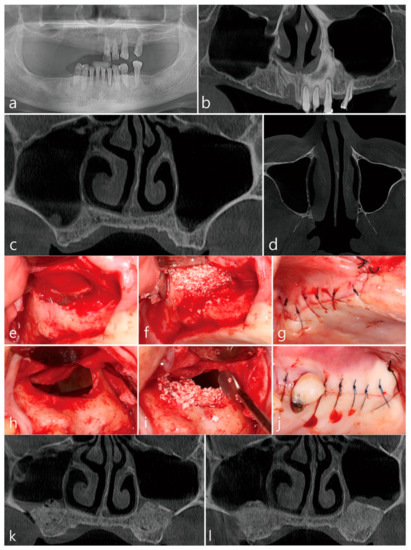

Implant treatment planned on a 72-year-old male smoker with no reported systemic conditions who previously used removable partial dentures. Panoramic imaging confirmed left and right maxillary sinus pneumatization with atrophied ridges. The height of the residual crestal bone on the panoramic radiography taken before surgery was approximately 1.0 mm in the right maxillary sinus and about 3 mm in the left maxillary sinus (Figure 3a,b). The CBCT taken before surgery confirmed no thickening of the Schneiderian membrane and thin lateral bone present over intended surgical site without the presence of the posterior superior alveolar artery. The maxillary ostium was open left and right (Figure 3c,d). In the lateral window approach performed in the right maxillary sinus, perforation of the Schneiderian membrane did not occur during the sinus floor elevation. The lateral bone lid was removed (Figure 3e). Osteon III (Genoss, Suwon, Korea) was filled in the elevated sinus, and the lateral window site was covered with a collagen membrane (Genoss, Suwon, Korea) (Figure 3f). The mucoperiosteal flap was closed (Figure 3g). In the lateral window approach performed on the left maxillary sinus, the membrane was perforated during sinus floor elevation. The lateral bone lid was pushed up while attached to the sinus membrane (Figure 3h). According to the modified proposed protocol of the open lateral window technique, the sinus floor was filled with Osteon III (Genoss, Suwon, Korea) and the upper part of the lateral window site was opened. Lateral window sites were not covered with a collagen membrane (Figure 3i). The mucoperiosteal flap was closed (Figure 3j). Post-operatively, intermittent nasal bleeding on the perforated sinus side with minor facial swelling and pain were noted for one week. Thereafter, no sinonasal complications were observed. In the coronal image of the CBCT taken immediately after surgery, no displacement of the bone graft particle was observed in the left and right sinus bone grafts (Figure 3k). In the coronal image of the CBCT taken 6 months after surgery, there was little change in the volume of the left and right sinus bone grafts, and minimal membrane thickening was observed only in the left maxillary sinus bone graft. All exposed bone graft substitutes were covered with soft tissue (Figure 3l).

Figure 3.

Case 3. (a) Preoperative panoramic radiograph. The right maxillary sinus was pneumatized and the residual alveolar bone was extremely insufficient. On the other hand, the left maxillary sinus was pneumatized, but some amount of residual alveolar bone was present; (b) Panoramic radiograph of preoperative CBCT scan. There was slight membrane thickening on the sinus floor, but the overall maxillary sinus was healthy; (c) Coronal image of preoperative CBCT scan. No blood vessels were observed at the site where the lateral window was to be formed, and the ostium was also open; (d) Axial image of preoperative CBCT scan. Sinus membrane thickening was not found. Lateral window approach with unintentional split-mouth design. (e) In the right maxillary sinus, there was no membrane perforation during sinus floor elevation. The MSA was performed using Osteon III. The lateral window site was covered with a collagen membrane; (f) In the left maxillary sinus, the Schneiderian membrane was widely perforated during sinus floor elevation. After bone grafting with Osteon III only on the sinus floor, the upper portion of the lateral window site was opened; (g) The flap was closed; (h) The left maxillary sinus was widely perforated during sinus floor elevation via the lateral window approach. Lateral bone window was pushed up; (i) Bone grafting was performed only on the sinus floor, and the upper lateral window site was opened. Membrane covering was not applied; (j) The mucoperiosteal flap was closed. (k) Coronal image of CBCT taken immediately after surgery. No leakage of the bone graft substitute was observed from the left maxillary sinus bone graft where the maxillary sinus membrane was perforated; (l) Coronal image of CBCT scan 6 months after surgery. A slight membrane thickening was observed in the left maxillary sinus compared to the right maxillary sinus where the perforation of the Schneiderian membrane occurred.